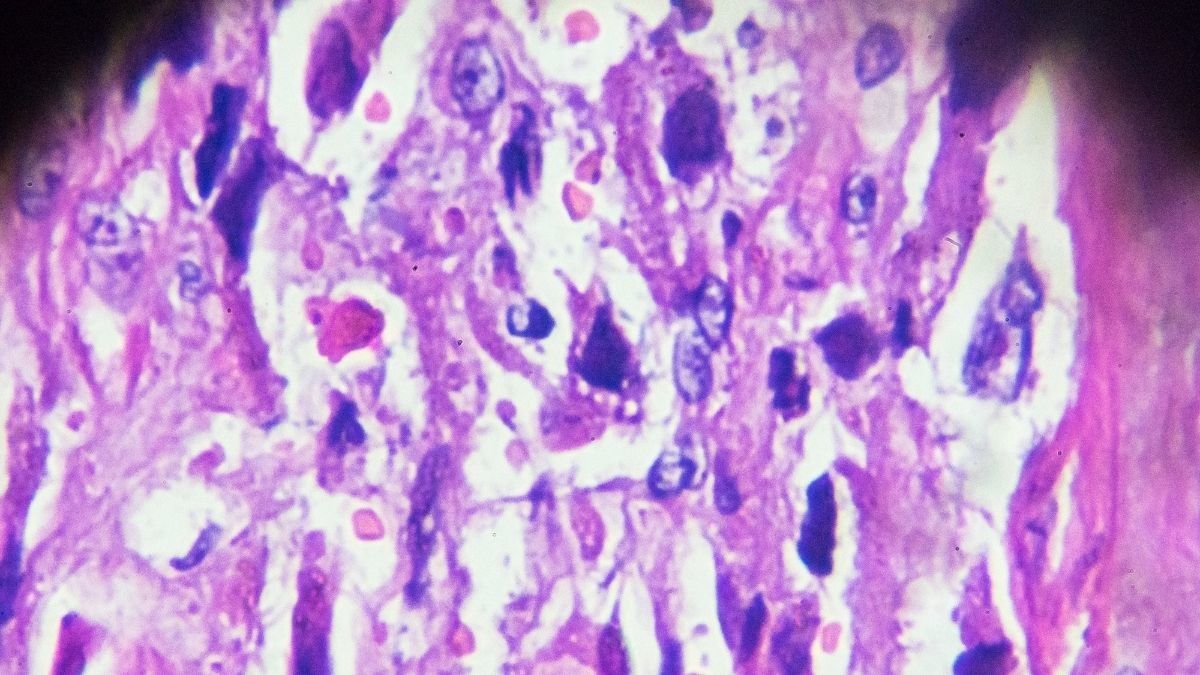

Mengutip Medical News Today, koriokarsinoma merupakan bentuk lain dari penyakit trofoblas gestasional (PTG). Pada kondisi ini, tumor tumbuh dari sel abnormal di dalam rahim.

Perkembangan PTG berawal dari sel-sel yang biasanya menjadi plasenta selama kehamilan. Sel-sel ini disebut sel trofoblas, yang berfungsi membantu embrio menempel pada rahim dan membentuk plasenta.